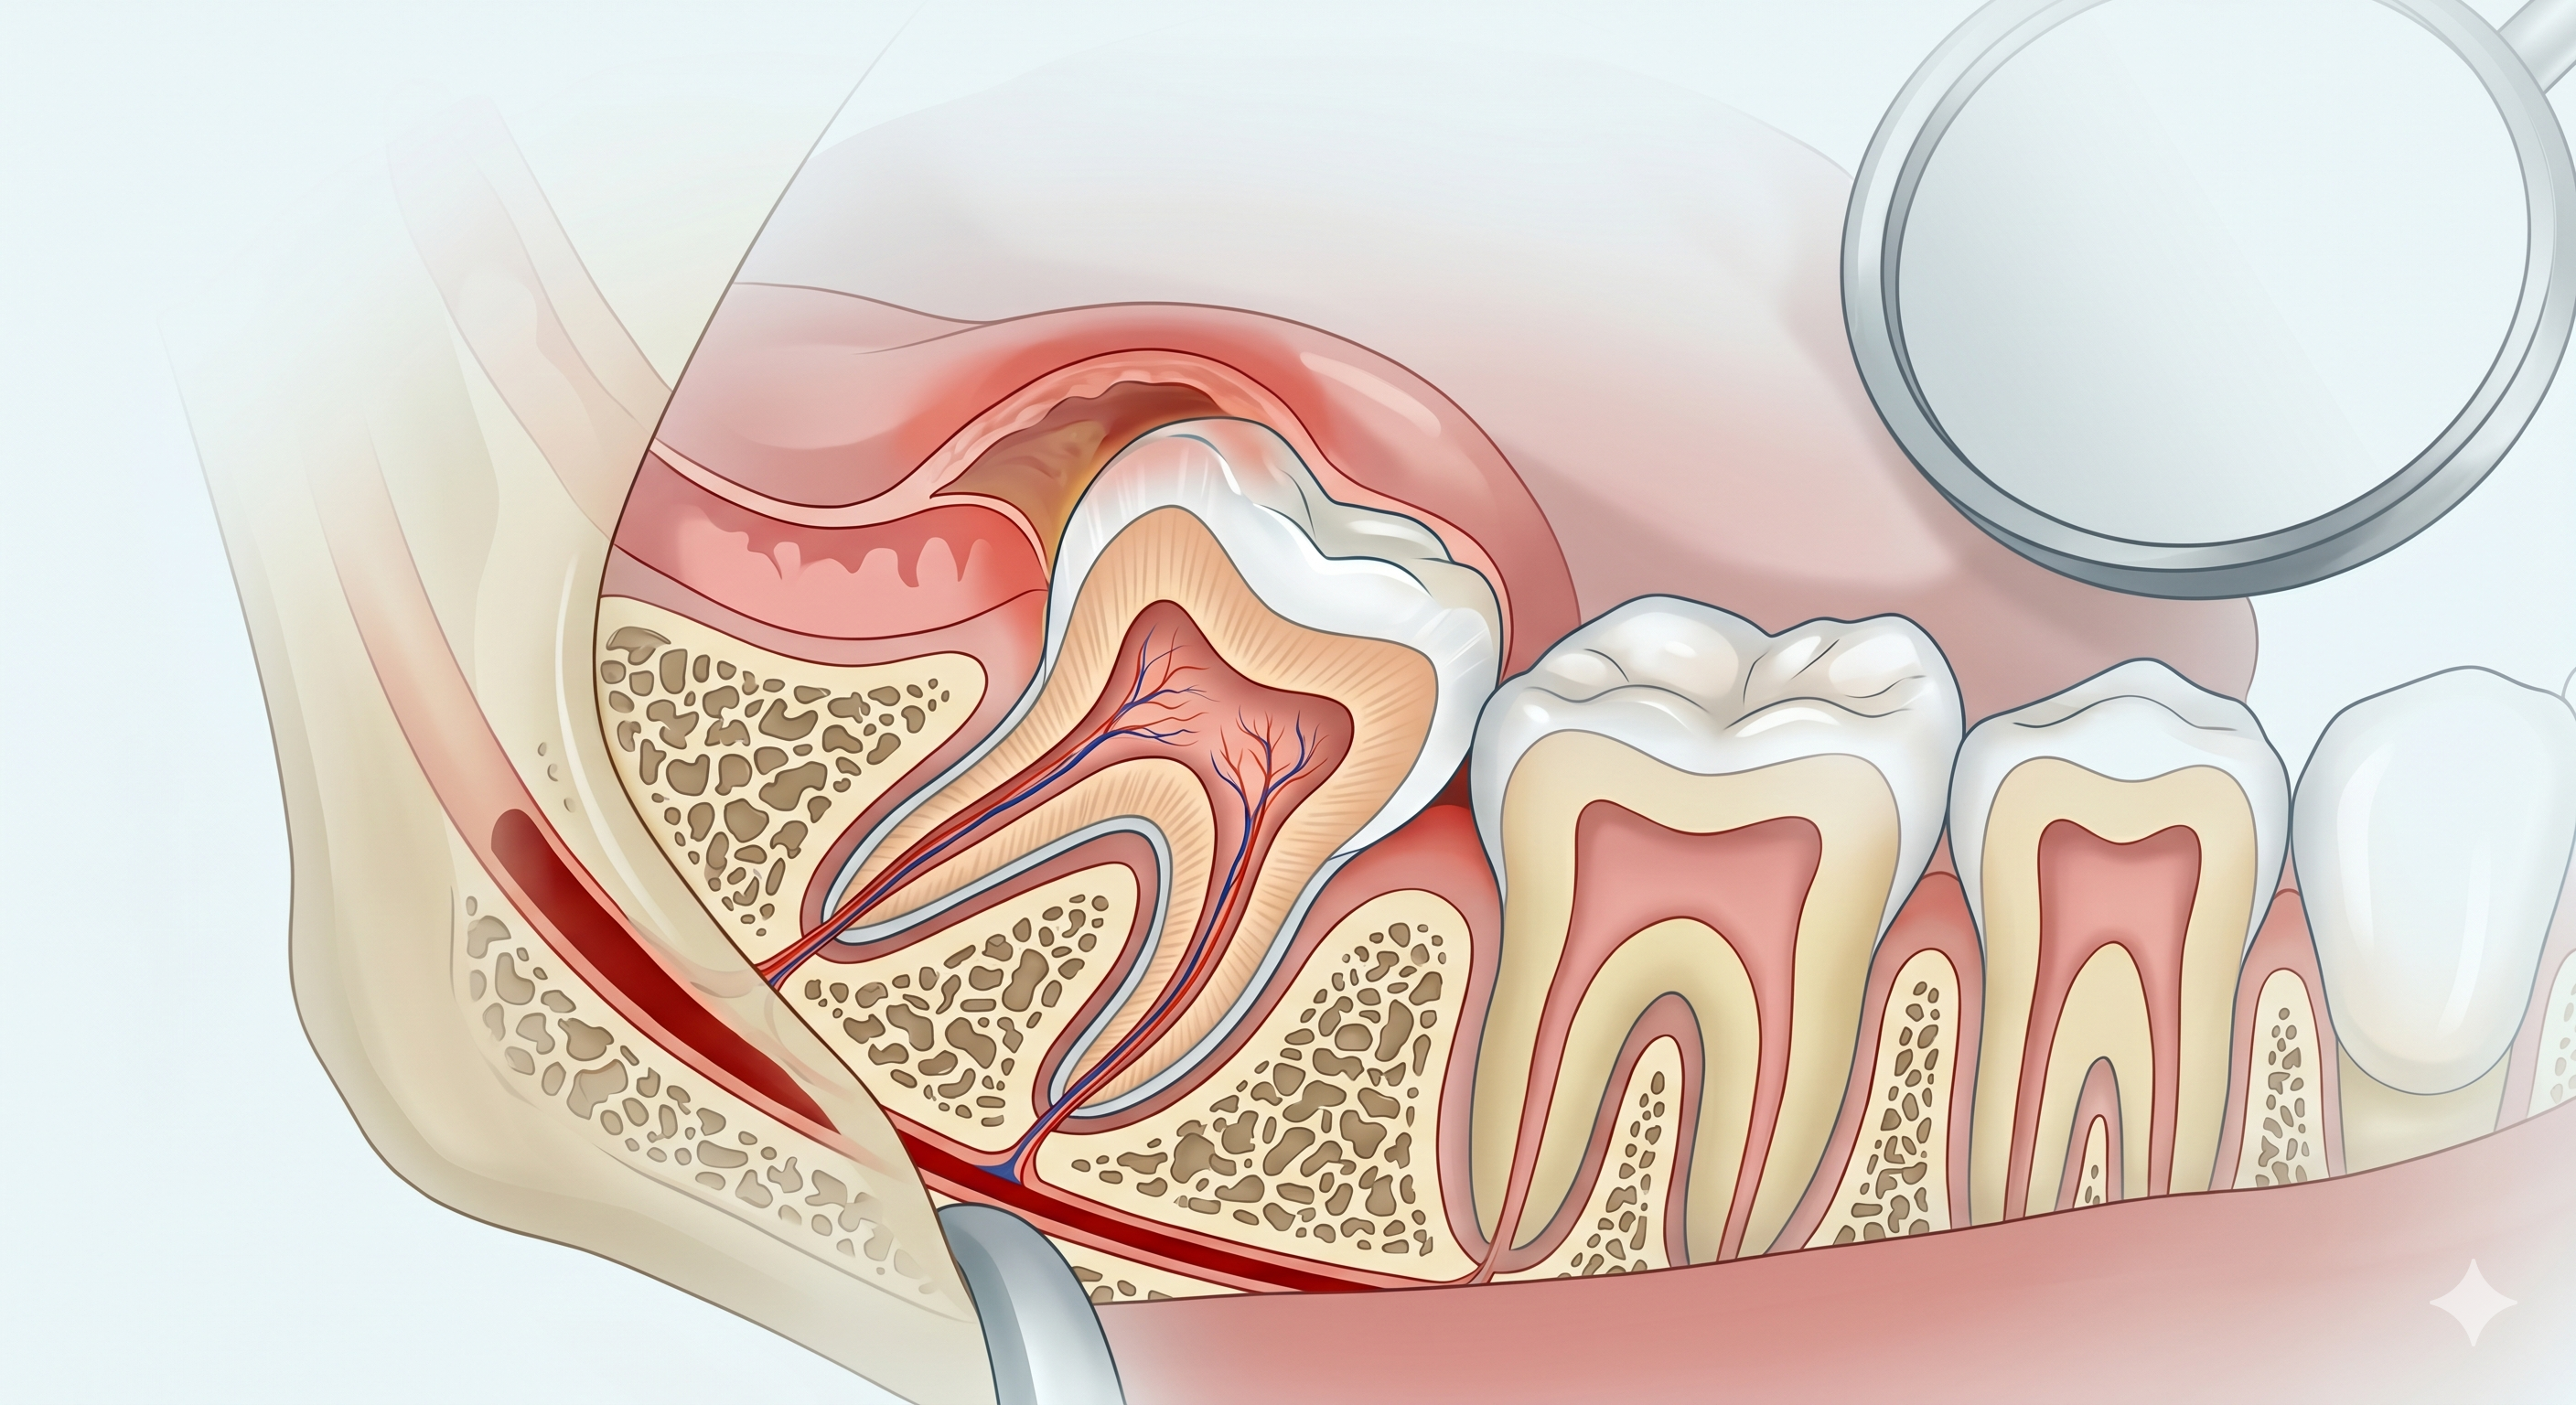

Dr Kwa Zheng Kang

Specialist Endodontist

Dr. Kwa is a specialist in Endodontics with over a decade of clinical experience. After obtaining his DDS in 2012, he pursued advanced training in Spain to master microscope-aided dentistry. Known for handling complex root canal cases and surgical retreatments, Dr. Kwa is also a prominent international speaker, having conducted workshops across Asia and the Middle East. His academic work is published in peer-reviewed journals, and he is recognized globally for his excellence in clinical techniques.